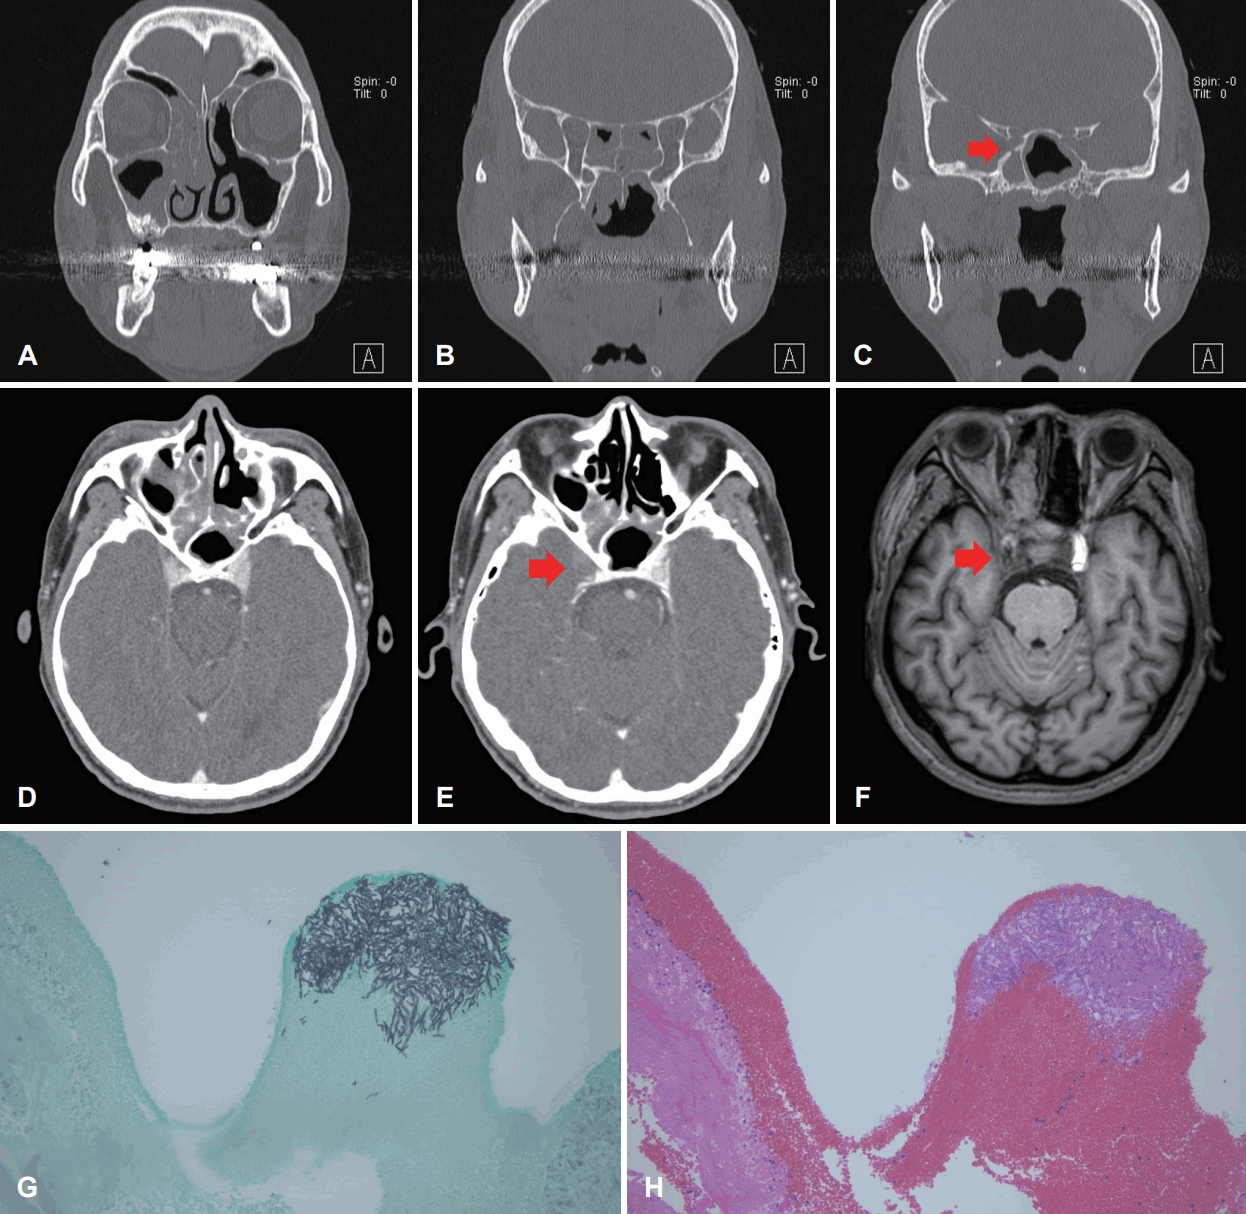

A 63-year-old male visited the emergency room (ER) complaining of a change in mental wellbeing and right-sided weakness. He had a medical history of hypertension and diabetes mellitus, and was currently taking medication for chronic headaches prescribed by our Department of Neurology. The patient had taken a brain MRI scan 2 months earlier due to chronic headache, and the radiologists interpreted it as a simple chronic sphenoid sinusitis (Fig. 2A and B). A week earlier before his visit to our ER, the patient had been admitted to our Department of Endocrinology due to uncontrolled diabetes and during his hospitalization, he received otolaryngology treatment due to headache suspicious of originating from sinusitis. At the time, the otolaryngologist recommended PNS CT, but the patient had refused to proceed. Upon neurological examination during his present visit in the ER, his mental status was assessed as deep drowsy, with right upper extremity motor: 3/5 grade, right lower extremity motor: 3/5 grade, left upper extremity motor: 4/5 grade, and left lower extremity motor: 4/5 grade. Both feet showed positive Babinski sign with accompanying neck stiffness. A contrast enhanced brain MRI scan was taken, and was reported to show an acute infarct in the left thalamus, left temporal lobe medial portion, internal capsule, left basal ganglia, and left occipital lobe, as well as a density change in the left sphenoid sinus and obstruction in the left ICA (Fig. 2C-E). Spiral CT 3-D common carotid angio + brain perfusion results showed total obstruction in the left ICA, and the left middle cerebral artery was supplied by the anterior communicating artery and posterior communicating artery. During his initial stay in the ER, the neurologist suspected invasive fungal sinusitis and referred him to our department for further evaluation and management.

Consecutive MRI, paranasal CT and pathologic findings of a 63-year-old male who had a history of hypertension and diabetes in Case II. A: Brain MRI, left sphenoid sinus showing hypointensity compared to surrounding bone density on T1-weighted images. B: Brain MRI, marked hypointensity of the left sphenoid sinus on T2-weighted images. C-E: Brain MRI showing acute infarct in left thalamus, left temporal lobe medial portion, internal capsule, left basal ganglia, left occipital lobe and left ICA obstruction. Left ICA obstruction observable with destruction in the medial part of the bone. F and G: CT scan showing left cavernous sinus involvement due to left sphenoid sinus fungal sinusitis with obstruction seen in the left ICA. H: Aspergillosis invades adjacent mucosa (arrows). I: High-power image of hyphae of aspergillosis. Original magnification: H, H&E stain ×200; I, H&E stain ×400. ICA, internal carotid artery; H&E, hematoxylin and eosin.

During endoscopic examination, a whitish discharge was found in both nasal cavities. A PNS CT was taken, and a soft tissue mass was found in the left sphenoid sinus extending to and involving the left cavernous sinus (Fig. 2F and G). The radiologist diagnosed left ICA obstruction with left cavernous sinus involvement, due to mucocele or sinus fungal sinusitis in the left sphenoid sinus. Invasive fungal sinusitis was suspected and an emergency ESS was performed. During the surgery, a fungal ball was found in the left sphenoid, with dehiscence to the ICA wall. In order to confirm invasive fungal sinusitis, a biopsy was taken from the sphenoid wall. Voriconazole was given as antifungal agent, and the biopsy results reported aspergillosis (Fig. 2H and I). The patient has been in a coma for over 5 months after the surgery, and still remains in the neurological intensive care unit even at the time of writing of this paper.

In the second case, the patient presented with non-specific symptoms such as chronic headache which we were unable to associate with fungal sinusitis. In addition, physical examination and nasal endoscopy showed no findings that might have indicated fungal sinusitis. Upon examining his medical records more closely, the patient was noted to have had persistent headaches for the past year, and had received evaluation at our neurology department when the symptoms began to worsen 3 months earlier. Upon brain MRI, there were no other suspicious findings other than a fungal ball in the sphenoid sinus. The radiologist at the time diagnosed chronic sinusitis in the sphenoid sinus. Since the neurologist could not find any lesions in the brain, the patient was given medication merely for pain control.

As his symptoms persisted, the patient visited other local outpatient clinics and, upon blood-glucose monitoring, was found to have hyperglycemia. He was referred to our Department of Endocrinology for blood-glucose control, and was admitted for a week. During that week, the patient was referred to our department for headache evaluation, and was found to have no symptoms other than rhinorrhea, post-nasal drip and hyposmia due to chronic right nasal obstruction. No specific findings were present upon endoscopic exam, and since the patient refused to take another PNS CT, he was discharged for follow-up at our outpatient clinic. It was only 5 days after his discharge that he arrived back at our ER again due to a change in his mental status.

In retrospect, careful and meticulous observation of the brain MRI may have improved our diagnosis since the left sphenoid sinus showed a density change. Fungal sinusitis may have been suspected from these findings (Fig. 2A and B).